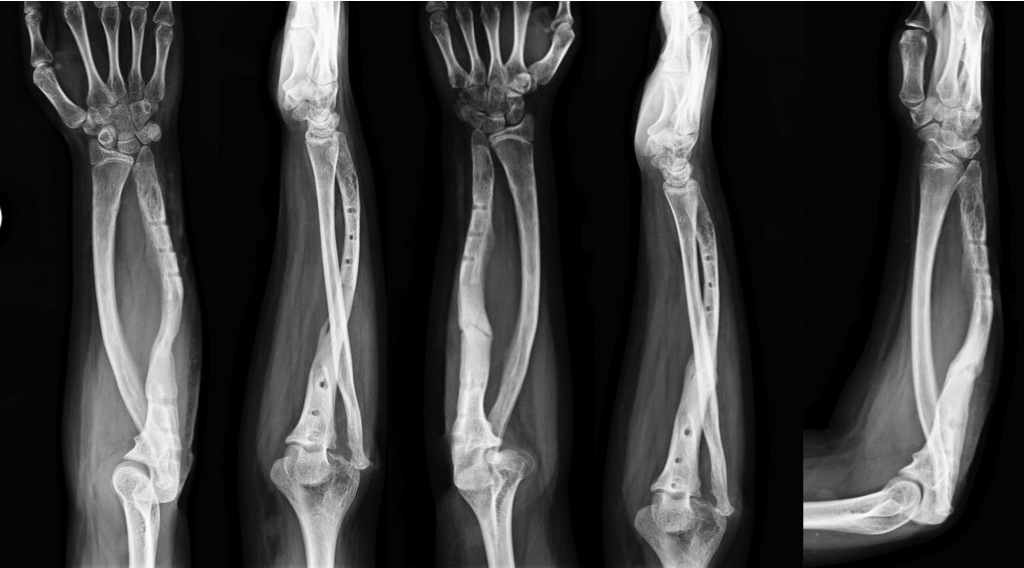

Deformările osoase